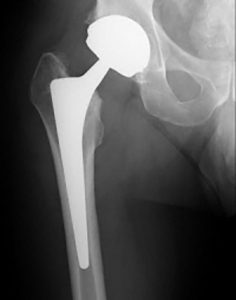

TOTAL HIP REPLACEMENT

MINIMALLY INVASIVE HIP REPLACEMENT